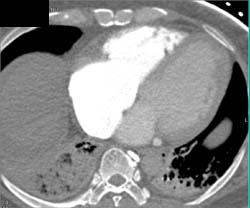

Tracheal Stenosis